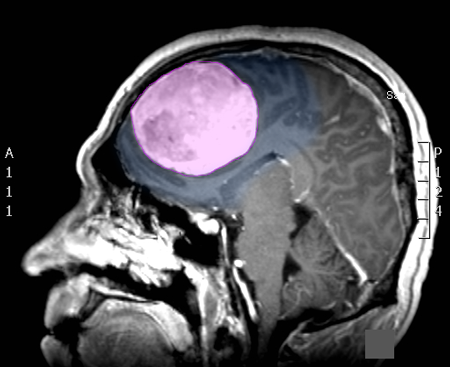

Διάγνωση Απαραίτητα είναι: Η λεπτομερής λήψη ιστορικού και η κλινική εξέταση, Η μαγνητική τομογραφία του εγκεφάλου με σκιαγραφικό, Σε ορισμένες περιπτώσεις: Η μαγνητική αγγειογραφία ή/και φλεβογραφία του εγκεφάλου, Η μαγνητική τομογραφία του εγκεφάλου με σκιαγραφικό για νευροπλοήγηση, Ηλεκτροεγκεφαλογράφημα και άλλες εξειδικευμένες εξετάσεις όπως μέτρηση οπτικής οξύτητας και οπτικών πεδίων προτείνονται κατά περίπτωση. |

Θεραπεία Η θεραπεία των μηνιγγιωμάτων που προκαλούν συμπτώματα είναι κατά κανόνα χειρουργική, και αυτό γιατί αποτελεί τον πλέον άμεσο και αποτελεσματικό τρόπο να αποσυμπιεστεί ο εγκεφαλικός ιστός ή τα κρανιακά νεύρα τα οποία πιέζονται. Στα ασυμπτωματικά μηνιγγιώματα η θεραπευτική σύσταση γίνεται ανά περίπτωση και η απόφαση εξαρτάται από πολλούς παράγοντες, όπως η ηλικία του ασθενούς, το μέγεθος και η θέση του μηνιγγιώματος, τα απεικονιστικά χαρακτηριστικά του, οι πληροφορίες που υπάρχουν από παλαιότερες απεικονίσεις για το ρυθμό ανάπτυξής του, κα. Όταν η θέση των μηνιγγιωμάτων ή η γενικότερη υγεία του ασθενούς δεν επιτρέπει ασφαλή χειρουργική παρέμβαση, τότε μπορεί |